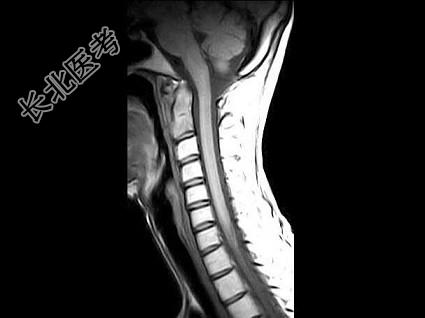

- 单项选择题女,29岁, 有午后发热,夜间盗汗, 消瘦等,枕颈部疼痛, 活动头部时加重,休息后减轻, 结合所提供的图像,最可能的诊断是 ( )

D、寰枢椎结核